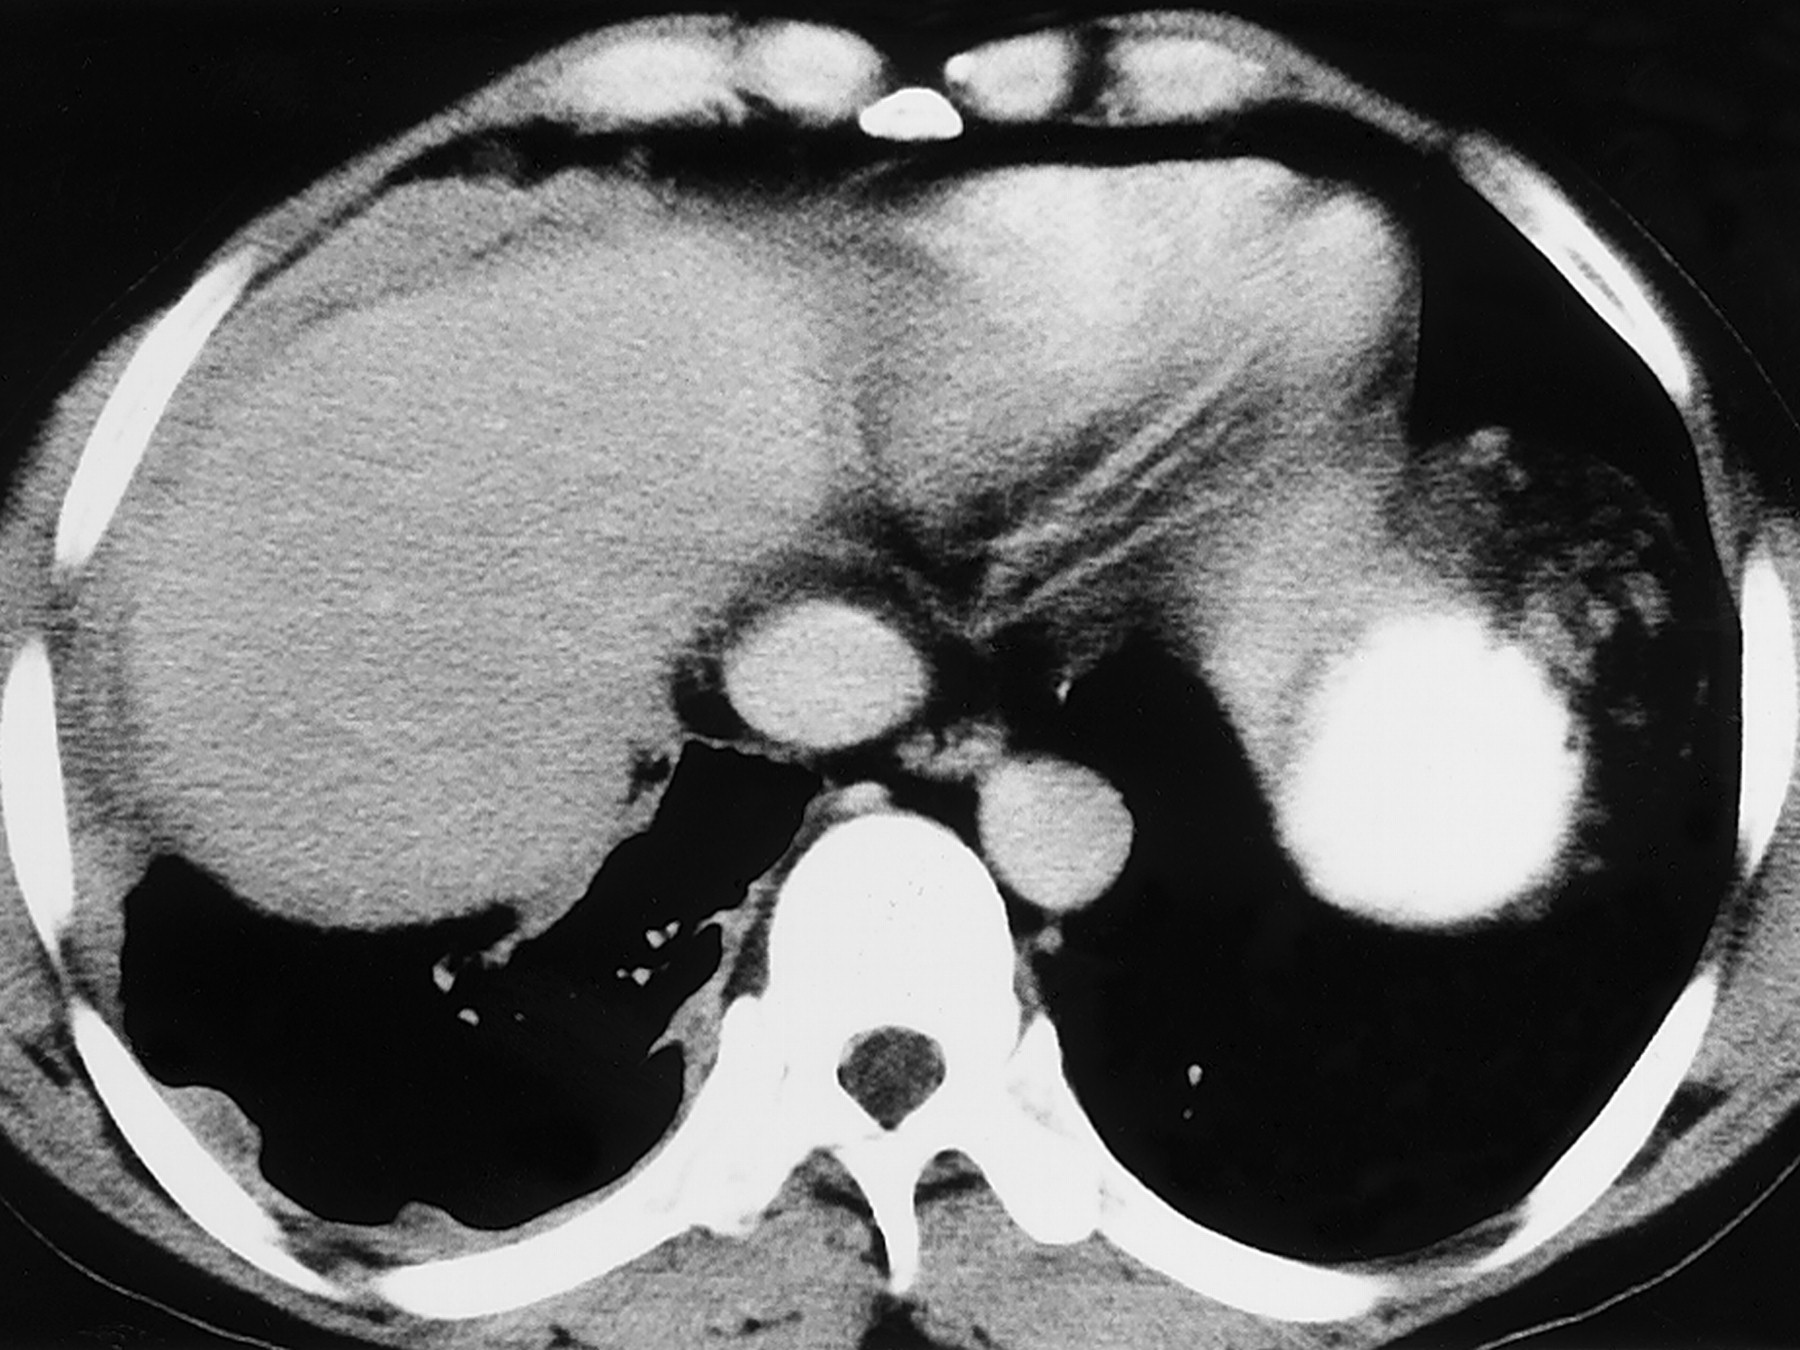

1) мезотелиома плевры и брюшины;

Злокачественная мезотелиома.

К осложнениям асбестоза относят рак легких. Сочетание асбестоза с раком легких и плевры встречается значительно чаще, чем с другими пневмокониозами, главным образом у мужчин. Рак легких в большинстве случаев развивается через 20-50 лет после начала работы в контакте с асбестовой пылью. Описаны случаи развития рака легких при стаже работы с асбестом менее 10 лет. Опухоли обычно локализуются в нижних долях легких. Механизм развития рака легких при асбестозе еще мало изучен. Считают, что иглообразные частицы асбестовой пыли, травмируя слизистую оболочку бронхов, вызывают ее гипер- и метаплазию, в дальнейшем происходит атипическое разрастание эпителия. Существует также мнение, что возникновению рака легких при асбестозе способствуют образующиеся у больных тяжелые бронхоэктатические изменения.